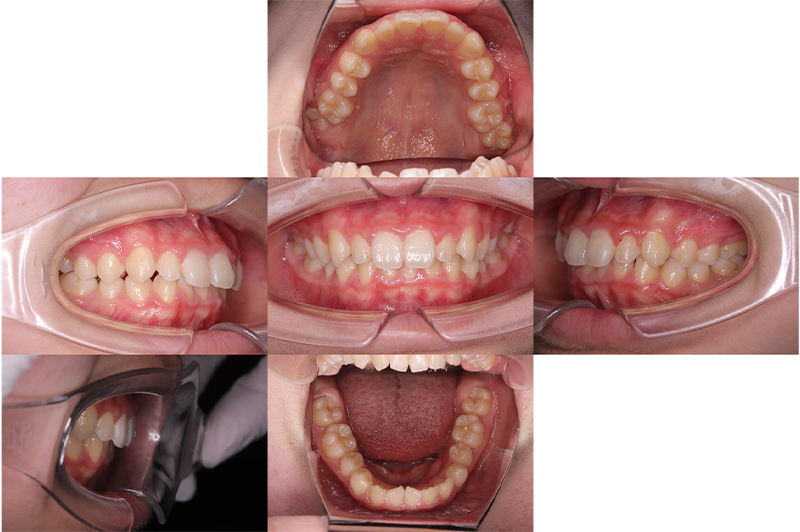

症例叢生

性別

期間6年5ヶ月

治療内容N-Bimler装置、Neo-Capを使用して治療

治療における

副作用・リスク

装着しないと効果は出ません

金額ビムラー装置:550,000円

ネオキャップ:4本

合計:572,000円